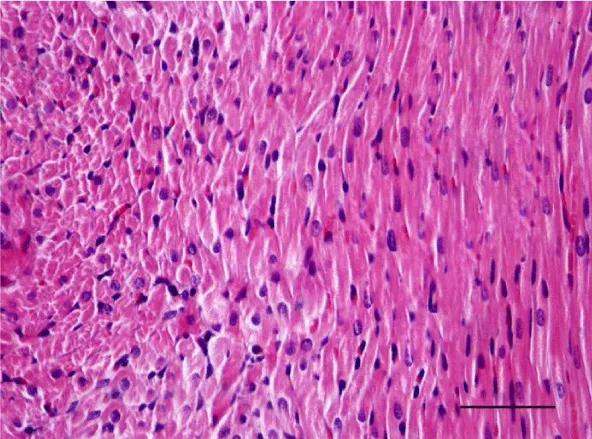

On H&E stained slides in 2-week-old rats, it was difficult to observe clearly defined longitudinal and transverse layers of cardiomyocytes in the wall of the left as well as the right ventricle. Cardiomyocytes appeared to be slightly eosinophilic and pronounced cross striation was not observed. They usually had one centrally located basophilic nucleus; in some cells, one or more nucleoli were noted. The perinuclear zone was well seen and was stained less intensively. The muscle fibers were enveloped by fairly thin connective tissue and a perimysium with abundant capillary network. It was fairly rare that fibroblastic nuclei were observed among the cardiac muscle cells (Figures 1,2).